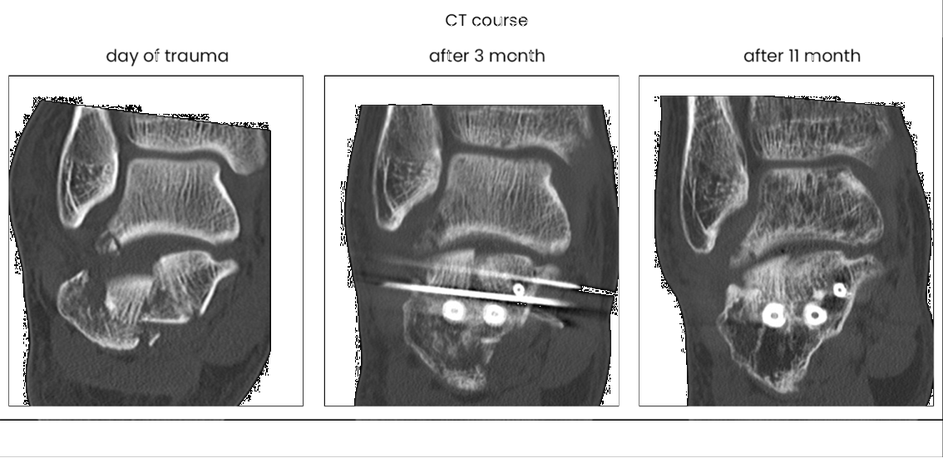

case 17BD, 47 years old, male, fall during work, 2 meters, "comminuted fracture", surgery after 2 days